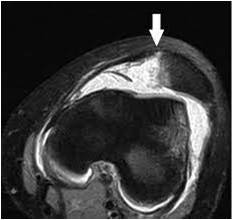

MRI-MPFL-tear

Patella dislocation – MPFL tear